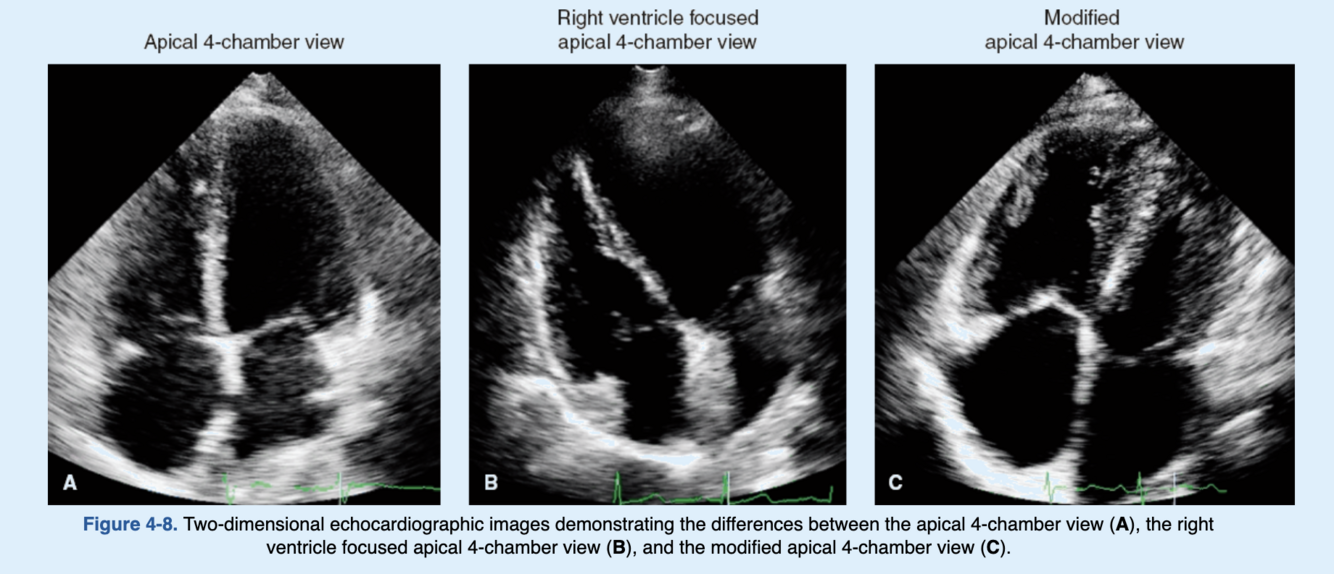

Which of the following is not a recommended view for assessing right ventricular function?

Apical 4-chamber view.

Right ventricle focused apical 4-chamber view.

Modified apical 4-chamber view.

Modified apical 3-chamber view.

The apical 4-chamber, right ventricle-focused apical 4-chamber and modified apical 4-chamber, left parasternal long and short axes, left parasternal RV inflow, and subcostal views are all recommended by the American Society of Echocardiography to adequately assess the right ventricle. The focused apical 4-chamber view is an optimal view for right ventricular measurements where the standard apical 4-chamber view is adjusted slightly to center the right heart on the screen and to ensure that there is no foreshortening. This is achieved by tilting the transducer in the apical 4-chamber view cranially and anteriorly. This is different from the right ventricle focused apical 4-chamber view where the transducer is tilted laterally and anteriorly (Fig. 4-8). The modified apical 3-chamber view is not a recommended view as it is a view that does not exist in the literature.

How to accurately trace the LA border?

When tracing the borders of the left atrium, the confluences of the pulmonary veins, and LA appendage should be excluded. The atrioventricular interface should be represented by the mitral annulus plane and not by the tip of the mitral leaflets